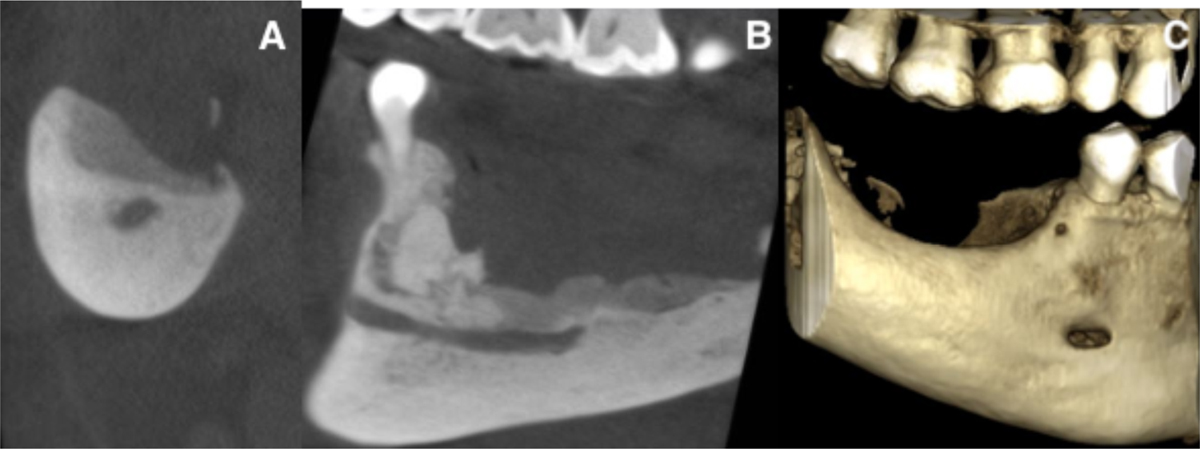

CBCT at the four-month follow-up. A: sagittal view. B: coronal view. C: 3D reconstruction.